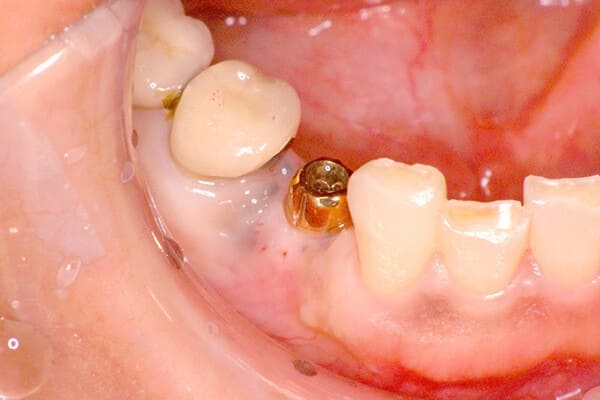

カスタムメイドアバットメントを連結、

セラミックの歯を装着する前

上のレントゲン写真を示した症例で、骨移植後、インプラントを埋入し、上部構造(歯の部分)がはいったところ。

ここまで骨がなくなってしまうと、骨移植をしても、前歯2本のうちの左側天然歯に比べて、その右側インプラントの歯では、やや歯肉が上がり、歯が長くなってしまっています(下左下の1枚目、2枚目の写真)が、